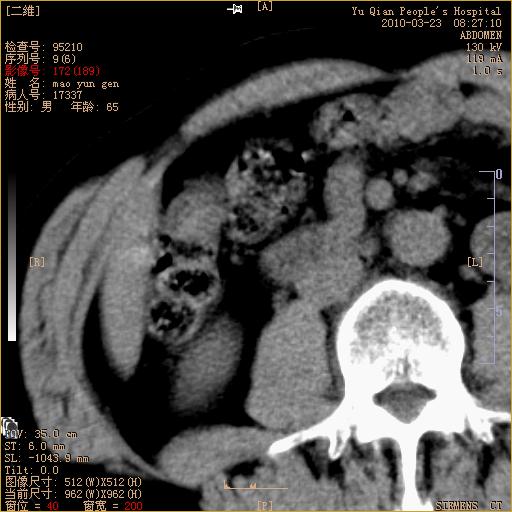

标题: CT25266:消瘦月余,前来肝部检查,请看看肠腔 [打印本页]

标题: CT25266:消瘦月余,前来肝部检查,请看看肠腔

肝区结肠占位,腺癌可考虑,建议肠镜活检。

升结肠肠壁增厚,不均强化,考虑升结肠腺癌可能性,建议肠镜检查。

1)考虑升结肠癌。2)右肾小囊肿。